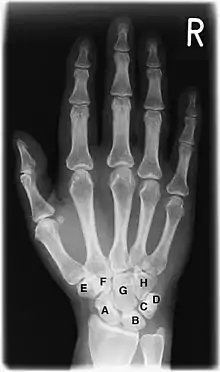

A Ладьевидная кость (Os scaphoideum)

B Полулунная кость (Os lunatum)

C Трёхгранная кость (Os triquetrum)

D Гороховидная кость (Os pisiforme)

E Кость-трапеция (Os trapezium)

F Трапециевидная кость (Os trapezoideum)

G Головчатая кость (Os capitatum)

H Крючковидная кость (Os hamatum)

Скелет кисти и лучезапястного сустава является наиболее удобным объектом для рентгенологического исследования развития костной системы человека[16]. На рентгенограмме кисти и лучезапястного сустава в прямой проекции видны ядра окостенения костей запястья, дистальных эпифизов лучевой и локтевой кости, наличие синостозирования эпифизов и диафизов. Сроки появления ядер окостенения и синостозирования зависят от пола и от возраста. Методика применяется для определения биологического возраста и его соответствия паспортному возрасту.

У доношенного новорожденного рентгенологическое исследование кисти и лучезапястного сустава в прямой проекции выявляет окостенение диафизов трубчатых костей, (развившееся из основных точек окостенения [или оссификации] начиная со второго месяца внутриутробного развития ребёнка), эпифизы трубчатых костей и кости запястья находятся на хрящевой стадии развития, поэтому на снимке не визуализируются. Иногда на рентгенограмме новорожденного выявляются точки окостенения головчатой и крючковидной костей, что дополнительно подтверждает доношенность новорожденного. В дальнейшем происходит последовательное появление ядер окостенения в костях запястья и эпифизах трубчатых костей. Наступление синостозирования эпифизов и диафизов трубчатых костей у мужчин происходит в возрасте 19—23 года, у женщин в 17—21 год. Современные исследования указывают на более ранние сроки синостозирования (закрытия хрящевых зон роста). Скелет лучезапястного сустава и кисти, состоящий из большого количества костей, претерпевает значительные возрастные изменения. Знание сроков и последовательности появления ядер окостенения позволяет профессионалам определить наличие эндокринной патологии и заболеваний других систем организма[16].